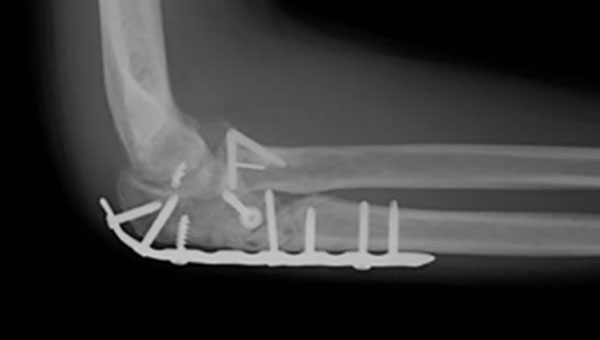

骨折した肘頭の骨片が多数にわたるときは、AOプレートを用いて固定します。

転位の少ないものは肘関節を90°に曲げた状態でギプスでの固定を4週間行います。転位の大きなものや粉砕骨折を合併したときなどは、観血的手術をして固定を行います。

観血的手術による固定方法としては、次の方法などがあります。

- 髄内釘・螺子による固定

- フックプレートによる固定

- Kワイヤーを8の字形に締結して引き寄せて固定するZuggurtung法(別名tension band wiring法)